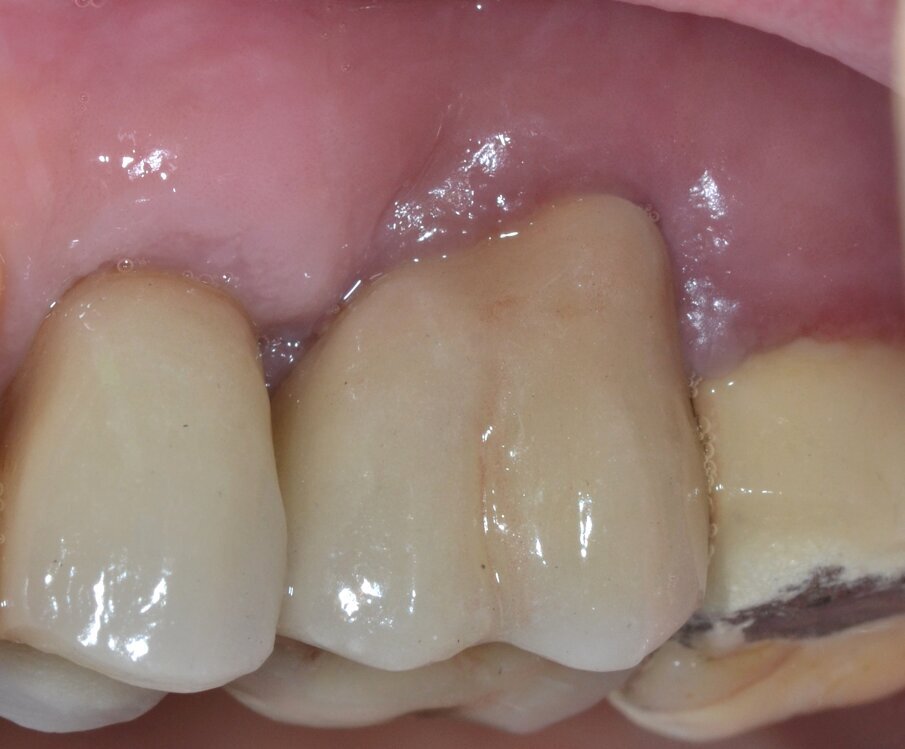

Paziente di aa 56, maschio, giunge alla nostra osservazione lamentando dolorabilità alla palpazione e alla masticazione in corrispondenza dell’elemento 1.6 sottoposto a terapia endodontica diversi anni prima. All’esame obiettivo si rileva la presenza di un’ampia raccolta ascessuale vestibolare associata a una profonda lesione parodontale nella zona della forcazione radicolare buccale (Fig. 1). Il sondaggio nel resto del cavo orale non evidenzia la presenza di altre lesioni parodontali (Fig. 2) mentre l’indagine radiografica rivela la presenza di un’ampia area di radiotrasparenza che coinvolge tutto lo spazio periapicale a partenza dalla radice mesio-buccale (Fig. 3). Sulla base dei dati clinici e radiografici acquisiti viene pertanto confermata la diagnosi di lesione endo-parodontale; nello specifico, si tratta di una lesione endodontica primaria con secondario interessamento parodontale e coinvolgimento della forcazione radicolare di Classe 3 secondo Hamp & Nyman3.

Fig. 2 - Sondaggio parodontale preoperatorio.